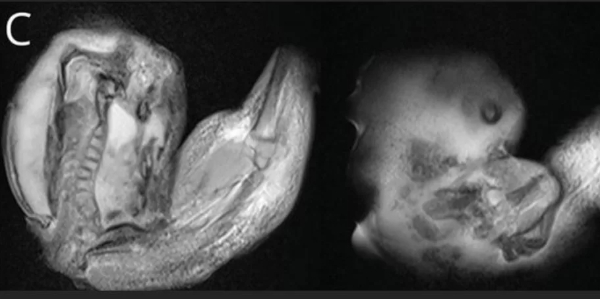

Imagens de tomografias computadorizadas mostraram que o feto, de aproximadamente 10 centímetros de comprimento, tinha desenvolvido os membros superiores, ossos e unhas, o que sugere que ele cresceu por alguns meses enquanto ainda estava no útero da mãe.

Menina passa por cirurgia para retirar feto de irmão gêmeo do crânio | Foto: Huashan HospitalFETUS IN FETU